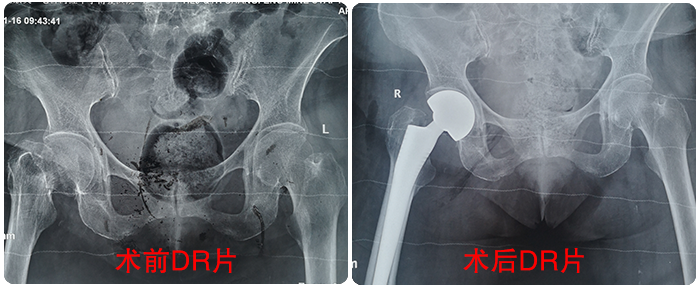

劉奶奶術(shù)前術(shù)後對(duì)比影(yǐng)像

劉奶奶術(shù)前術(shù)後對(duì)比影(yǐn♦§≥g)像